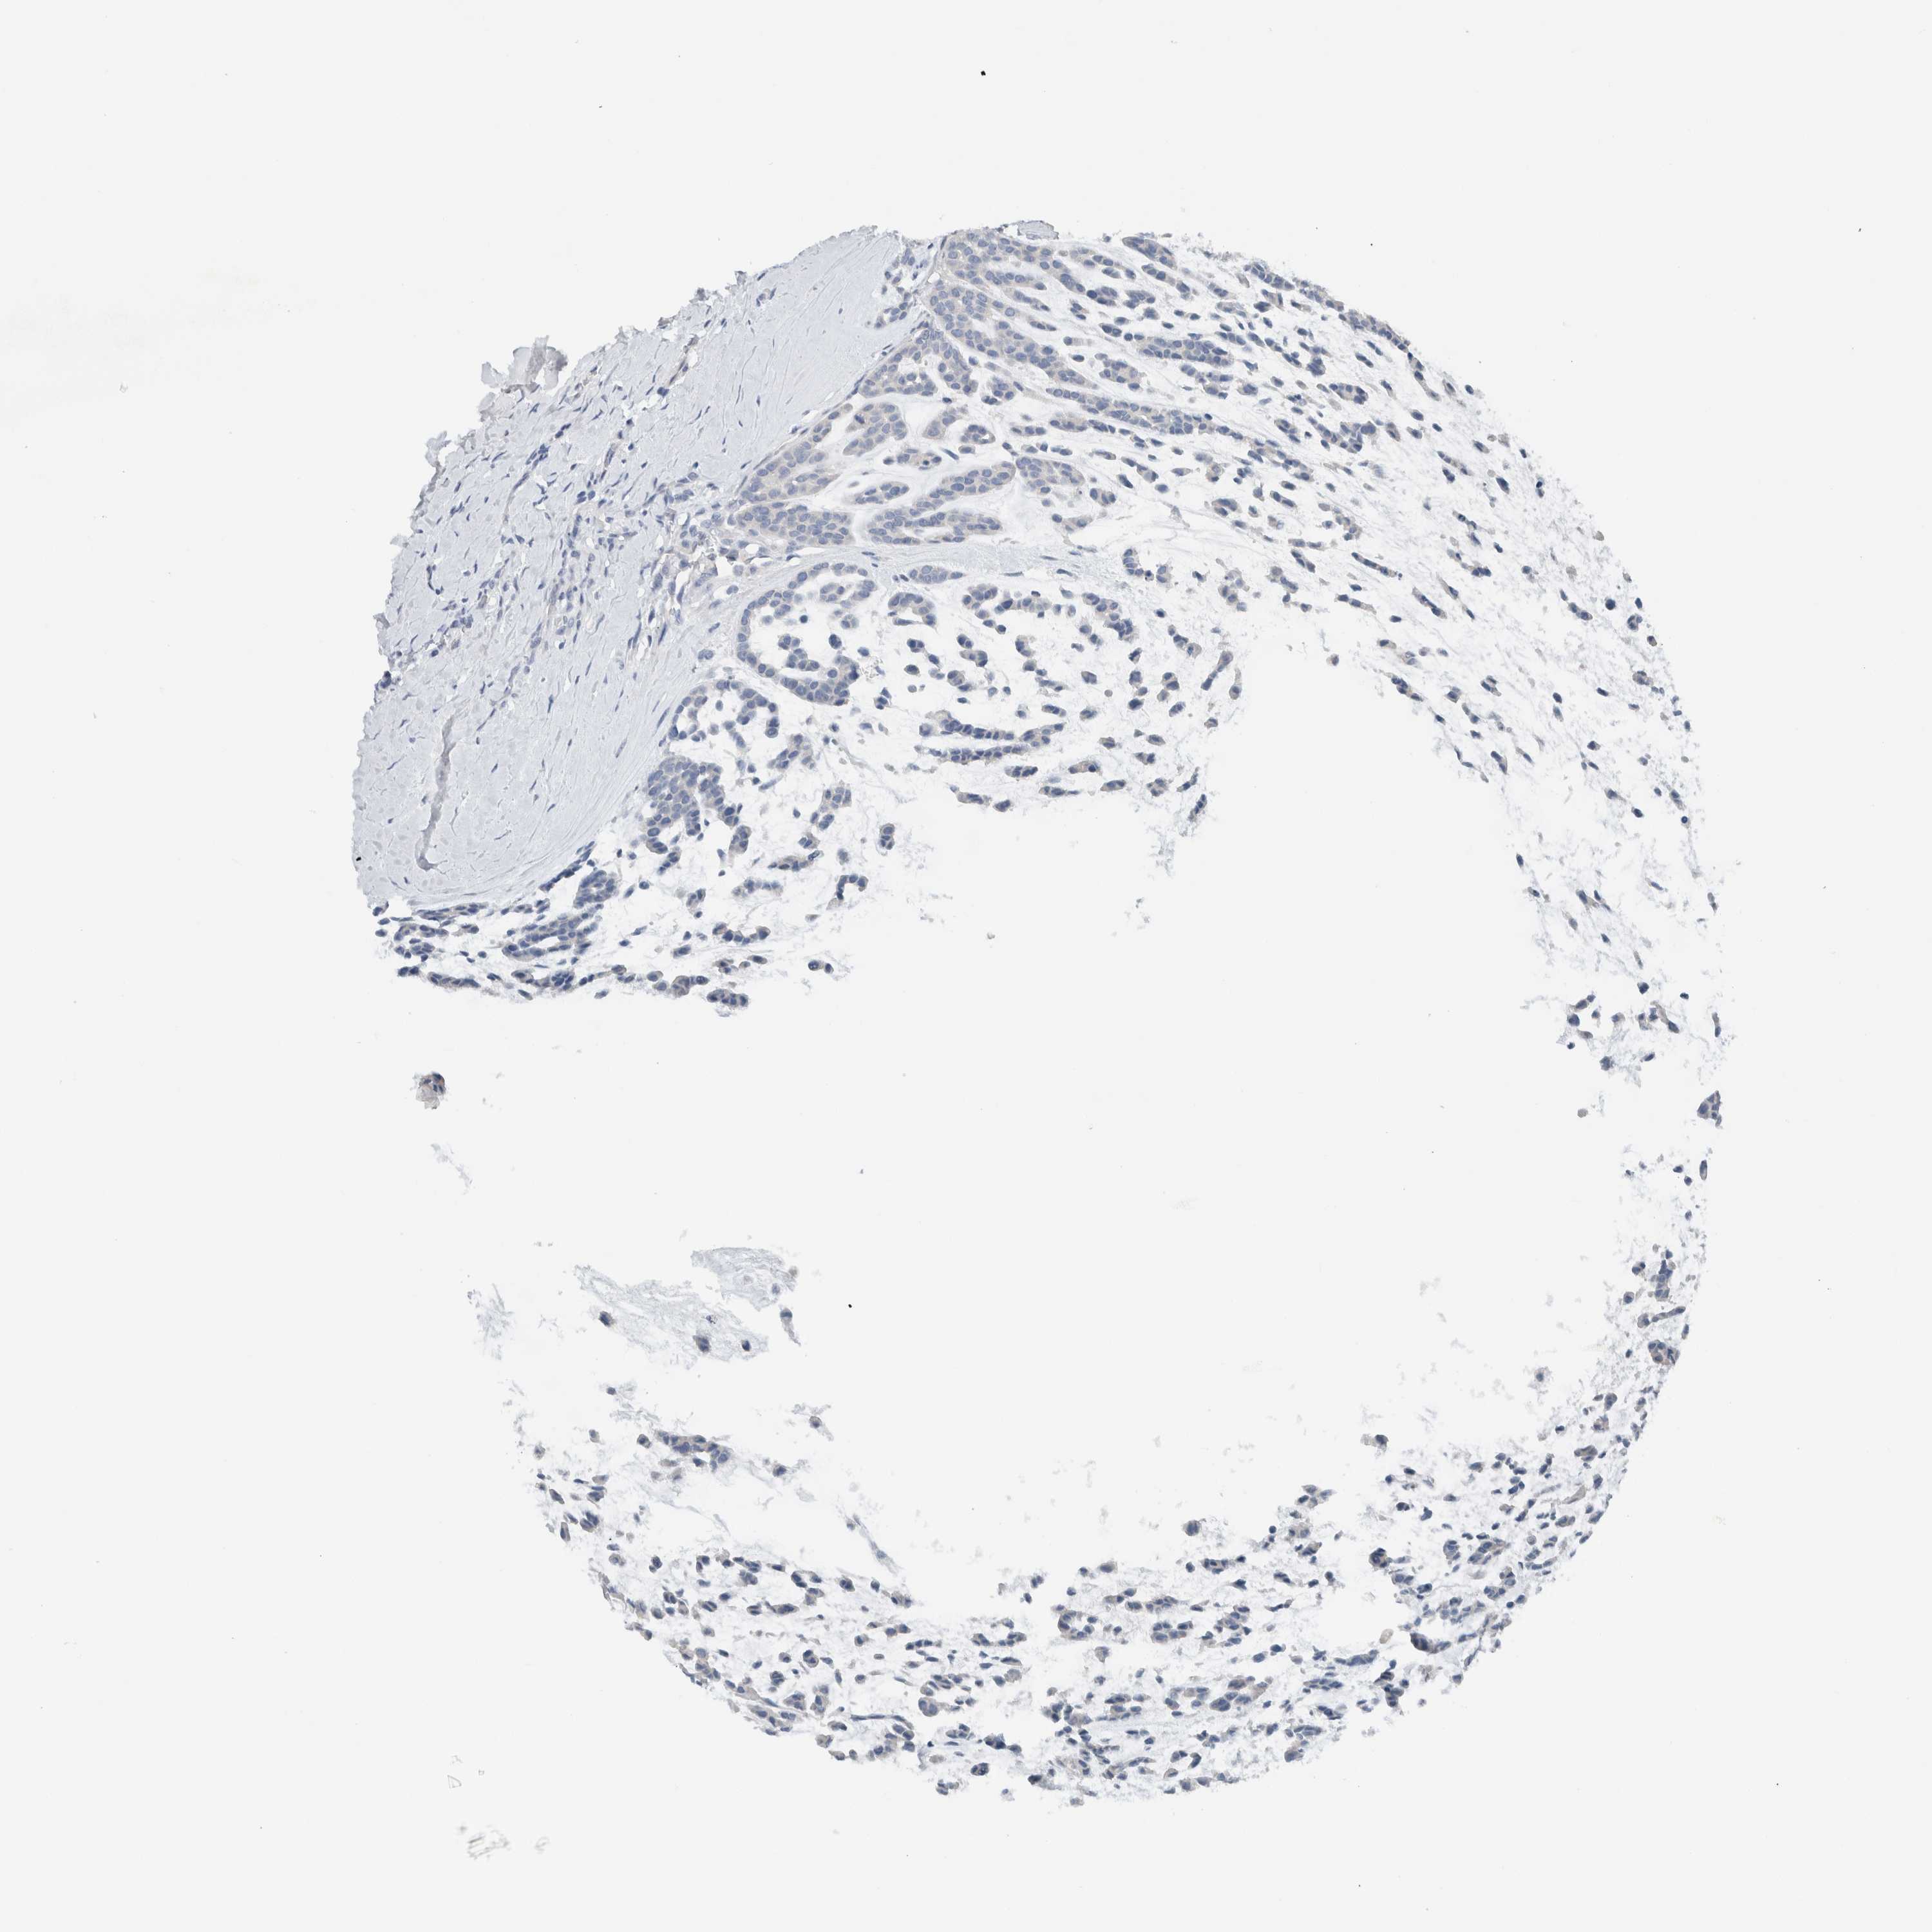

HEAD AND NECK CANCER - Protein expressioni

A mouse-over function shows sample information and annotation data. Click on an image to view it in a full screen mode. Samples can be filtered based on level of antibody staining by selecting one or several of the following categories: high, medium, low and not detected. The assay and annotation is described here.

Antibody stainingi

Antibody staining in the annotated cell types in the current human tissue is reported as not detected, low, medium, or high, based on conventional immunohistochemistry profiling in selected tissues. This score is based on the combination of the staining intensity and fraction of stained cells.

Each image is clickable and will lead to virtual microscopy that enables deeper exploration of all samples and also displays staining intensity scores, fraction scores and subcellular localization as well as patient and tissue information for each sample.

Antibody HPA023544

Staining

High

Medium

Low

Not detected

Intensity

Strong

Moderate

Weak

Negative

Quantity

>75%

75%-25%

<25%

None

Location

Nuclear

Cytoplasmic/membranous

Cytoplasmic/membranous,nuclear

Squamous cell carcinoma, NOS

Squamous cell carcinoma, metastatic, NOS

Adenocarcinoma, NOS

Adenoma, NOS